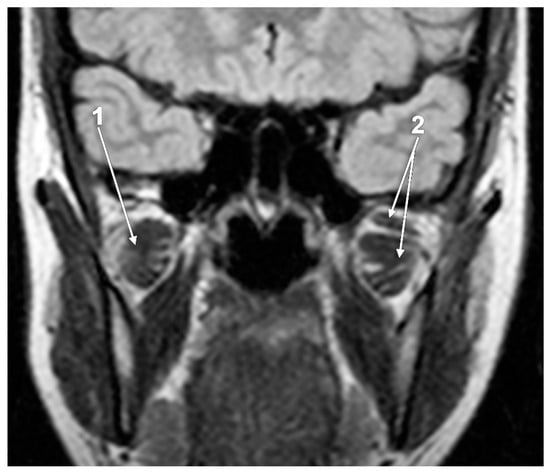

The Atrophy and Hypertrophy of the Lateral Pterygoid Muscle